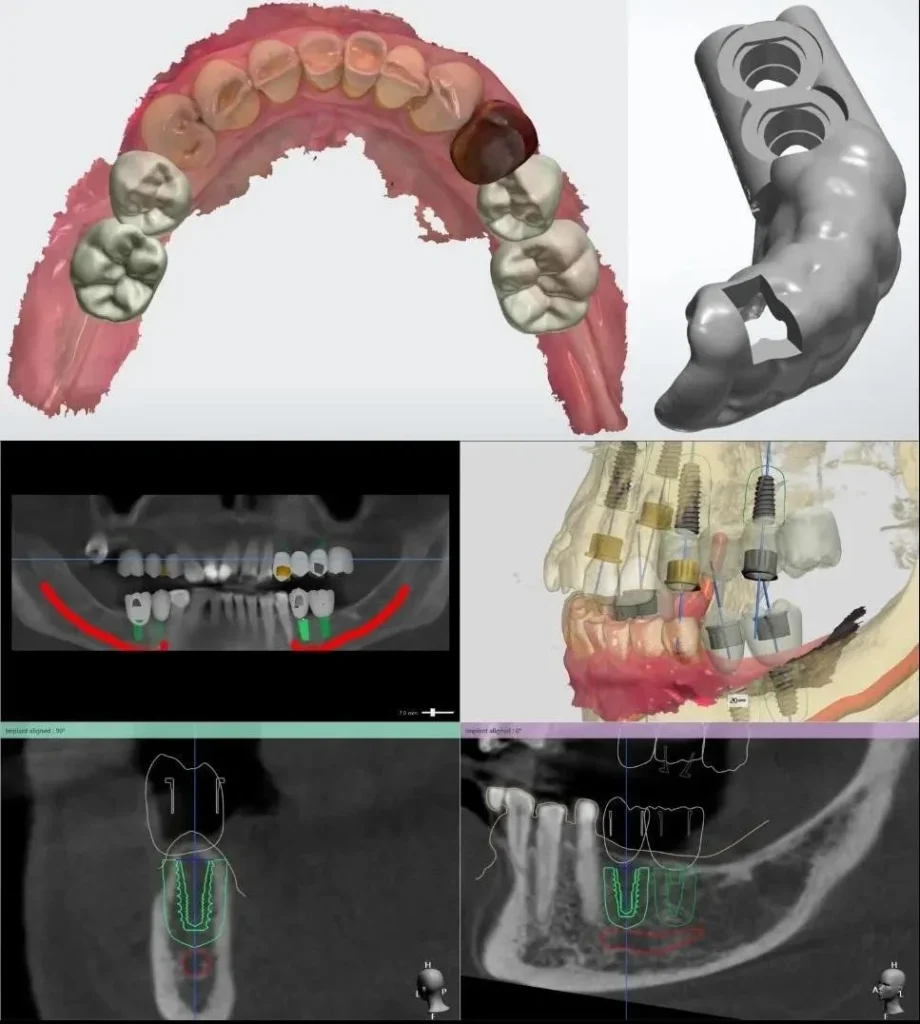

Step 1: Data acquisition, treatment planning, and guideline production.

At this stage, the dentist performs CBCT imaging and dental scanning. These data are imported into Exocad for treatment planning: implant position and angulation are precisely calculated based on Exocad force analysis. After determining the correct implant position, a surgical guide template is produced to ensure precise placement.

At this stage, periodontal tissues are also virtually reconstructed in their ideal state, and a customized anatomical healing abutment is produced along with the guide.

Feature 1: Precise implant placement within the jawbone in all 3 dimensions using the Guideline surgical guide.

Within the jawbone are dangerous anatomical structures such as the inferior alveolar nerve canal or the maxillary sinus that must not be damaged during implant surgery. Moreover, for an implant tooth to function well in mastication, the implant must be placed in the correct position and force axis.

When applying the personalized implant solution, the dentist uses Guideline technology to place the implant. Guideline enables precise implant positioning in three-dimensional space within the jawbone, making the surgery safer, improving chewing function, and enhancing long-term stability.